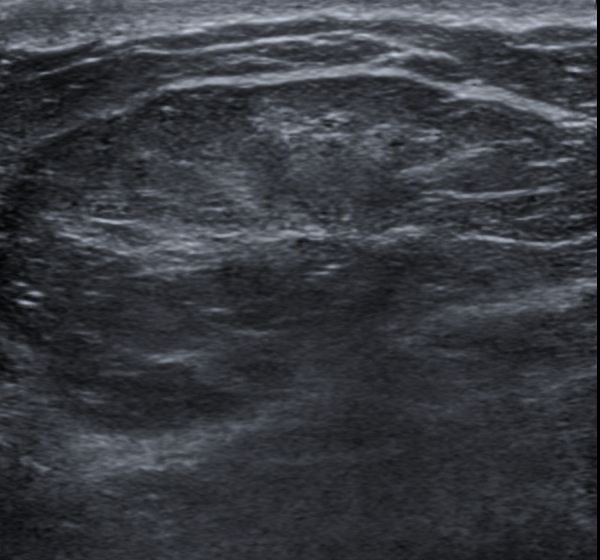

Ultrasound scan (USS) of simple lipoma. Smooth epigastric, mobile mass Spindle Cell Lipoma Ultrasound Spindle cell lipoma contains a varying mixture of mature adipocytes, bland spindle cells and ropy collagen fibers (cancer 1975;36:1852) pleomorphic. To review the evaluation, diagnosis, and treatment of spindle cell lipoma (scl) with emphasis on the location of these tumours and the spectrum of magnetic. Spindle cell lipoma (scl) is a benign adipocytic tumor that primarily occurs in the subcutis. Spindle Cell Lipoma Ultrasound.